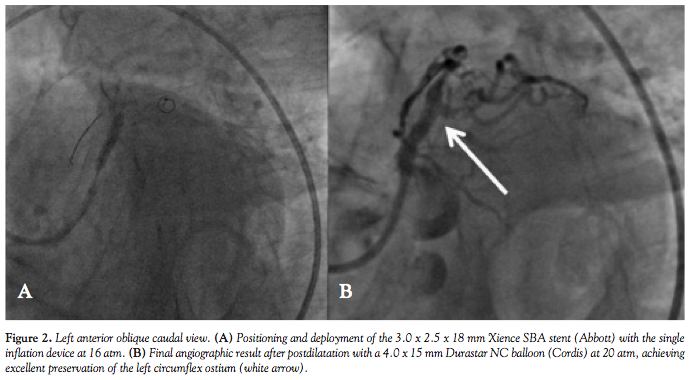

She was considered a candidate for percutaneous coronary intervention of the LMCA via the right femoral artery approach with a 7 Fr arterial sheath and EBU 3.0 guiding catheter (Medtronic Vascular). Two BHW guidewires (Abbott) were used. Using a dual-wire technique, the first was placed in the left anterior descending (LAD) coronary artery and the other in the LCX. Predilatation of both coronary arteries with a 3.0 x 15 mm Trek balloon (Abbott) at 16 atm was performed (Figures 1B and 1C). Following predilation, we implanted a 3.0 x 2.5 x 18 mm Xience SBA stent (Abbott Vascular) at 16 atm and subsequently postdilated it with a 4.0 x 15 mm Durastar NC balloon (Cordis) at 20 atm.

A satisfactory angiographic result was obtained with excellent preservation of the LCX ostium (Figures 2A and 2B). Our decision to utilize the Xience SBA stent in this case was based on our previous device success treating patients with complex coronary bifurcation lesions. The Xience SBA may represent a good alternative in lesions of this type and may help to avoid multistent techniques while preserving integrity of the side branch. To our knowledge, this is the first publication of Xience SBA stent usage in the invasive treatment of distal left main lesion.1-4